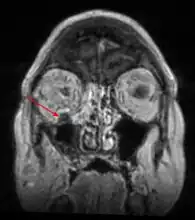

Imaging

Imaging is often performed, such as CT scan of lungs and sinuses.[38] Signs on chest CT scans, such as nodules, cavities, halo signs, pleural effusion and wedge-shaped shadows, showing invasion of blood vessels may suggest a fungal infection, but does not confirm mucormycosis.[16] A reverse halo sign in a person with a blood cancer and low neutrophil count, is highly suggestive of mucormycosis.[16] CT scan images of mucormycosis can be useful to distinguish mucormycosis of the orbit and cellulitis of the orbit, but imaging may look identical to those of aspergillosis.[16] MRI may also be useful.[39]

MRI head: right sided sinus involvement extending into the orbit.